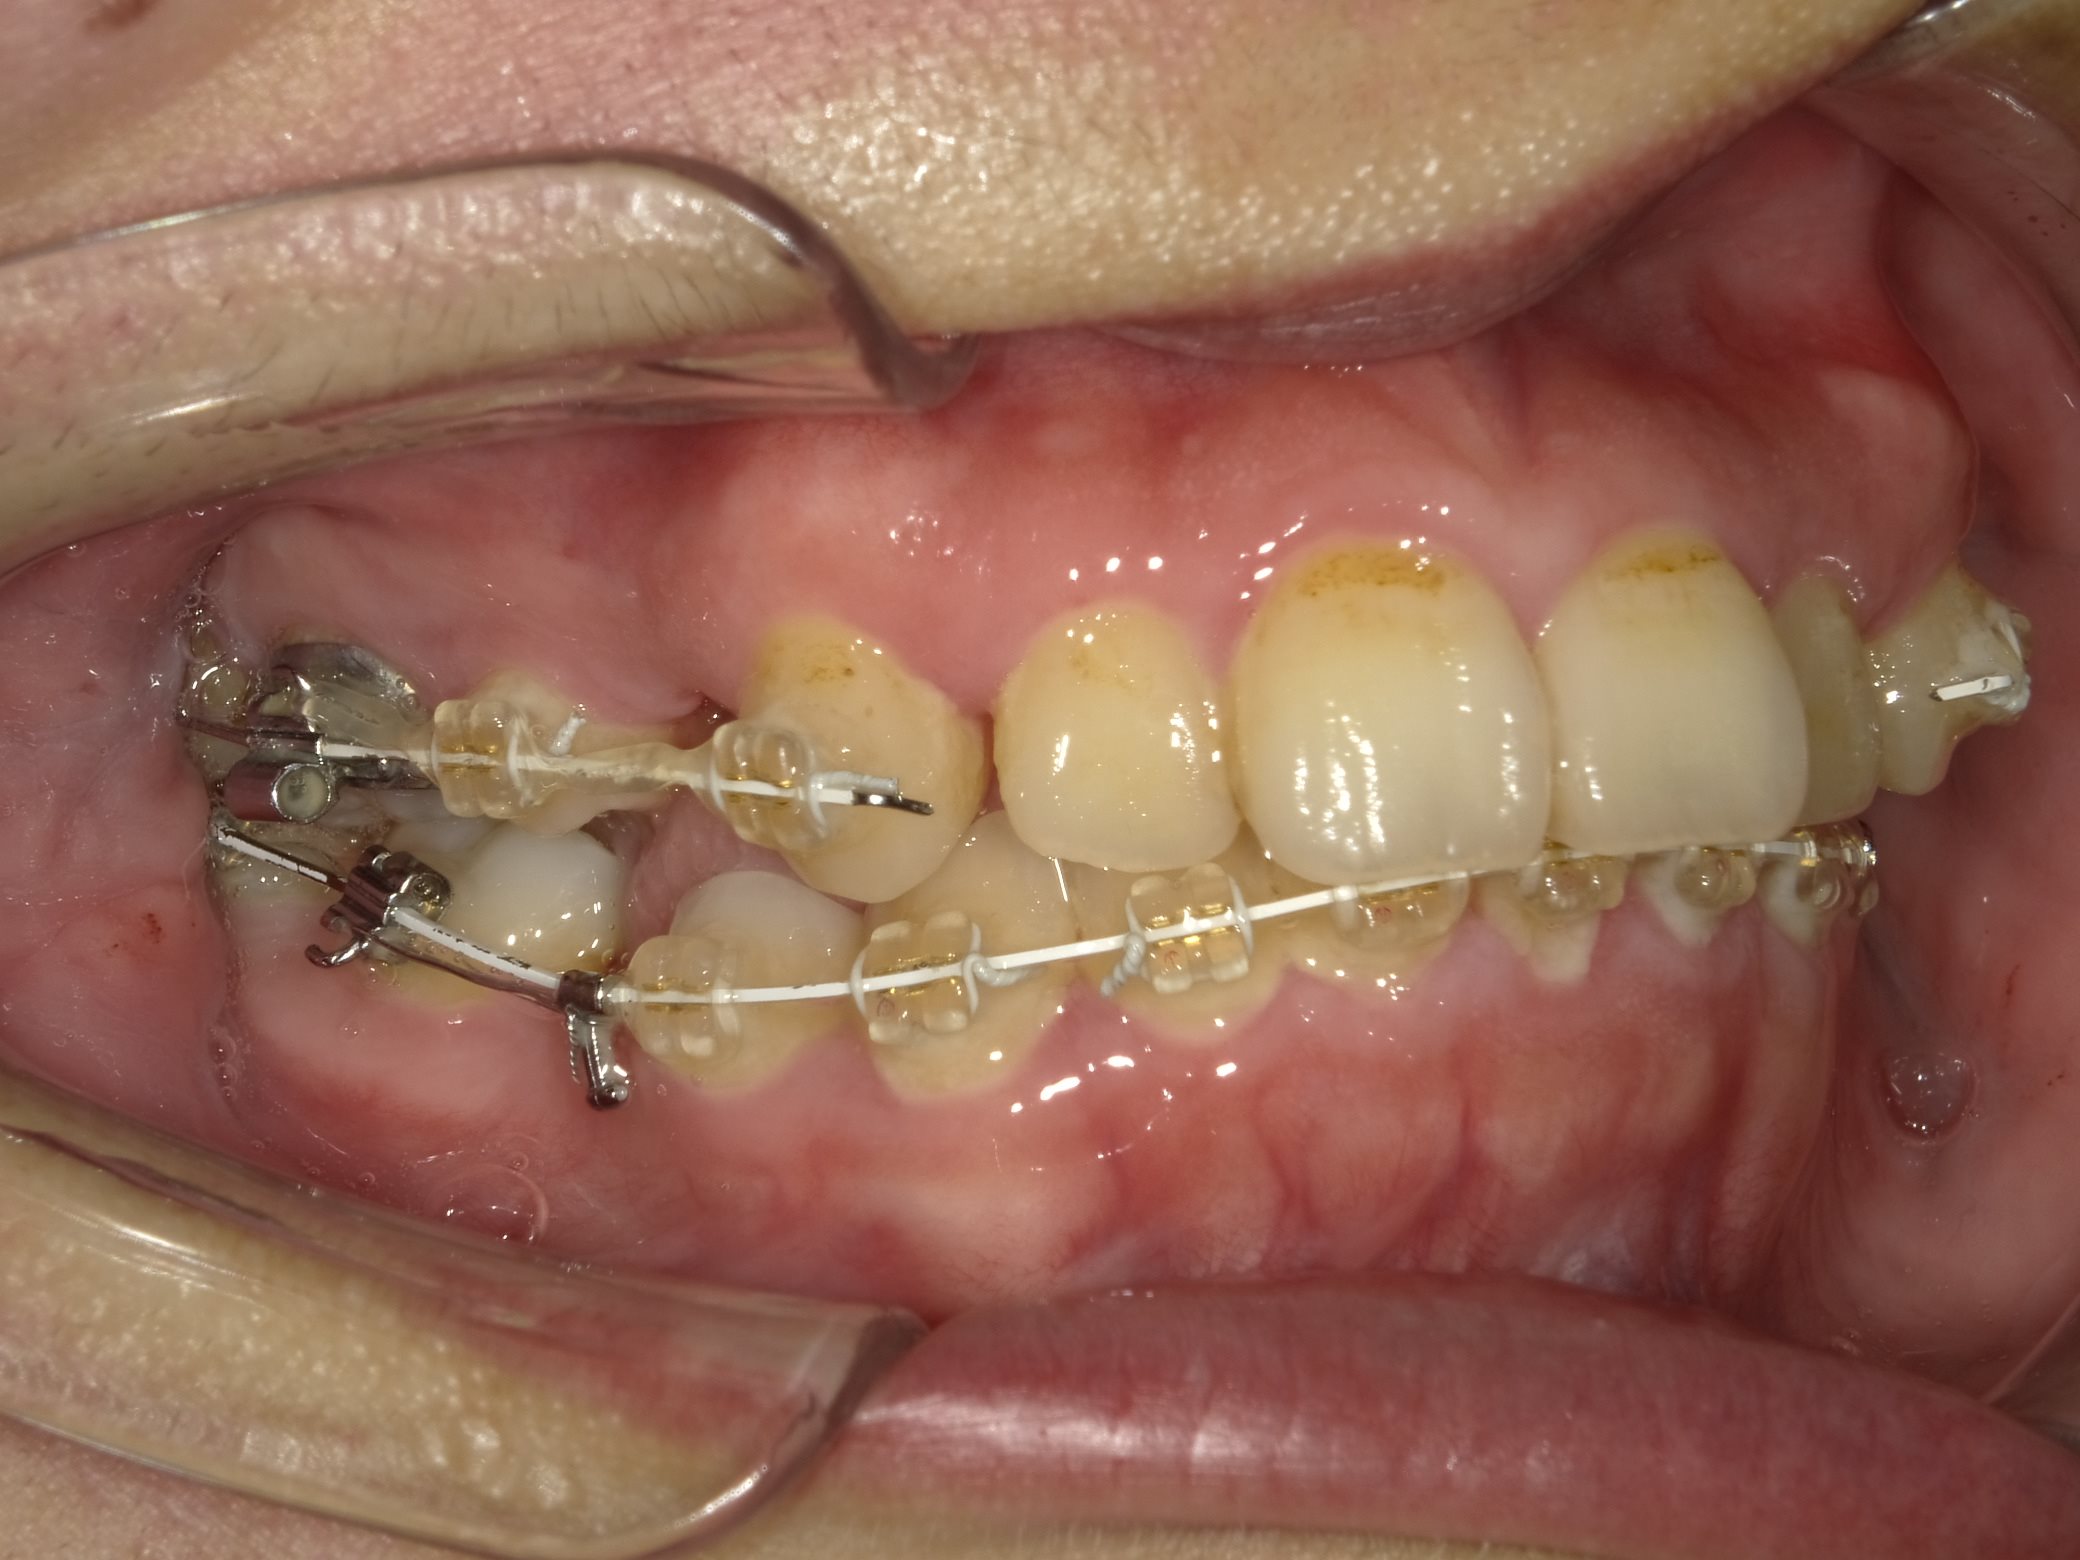

初診時の写真です。

上下とも顎の骨の大きさに対して歯が大きく、入りきっていないため、がたつきができています。

治療開始です。

上下の歯を抜歯し、まずは奥歯にのみ装置がつきます。

抜いたスペースを利用し、前歯を下げるため抜歯後早期に装置を取り付けます。

歯の動きを見ながら、前歯にも装置を取り付けていきます。

上の前歯にも装置がつき、少しづつワイヤーを太くしながら歯にかける矯正力を強くしていきます。

抜歯したスペースが小さくなってきているのが分かると思います。